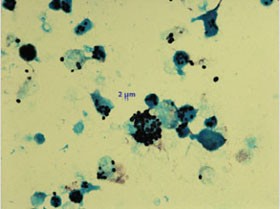

Abb. 1 und 2: Mikroskopie nach bronchioalveolärer Lavage (BAL).

Abb. 1: Erreger intrazellulär in Makrophagen

nach Versilberung. Abb. 2: Ebenfalls intrazelluläre Erregger in einer 4 Tage

bei 26°C inkubierten Anreicherung (ungefärbt). Hier sind bereits auskeimende

Pilzzellen erkennbar.

Der direkte Erregernachweis, z.B. aus Bioptaten, ist in jedem Fall anzustreben.

H. capsulatum ist bei einer generalisierten Infektion zu 72-90% aus dem Knochenmark, in 57-91% aller Fälle aus Blutkulturen anzüchtbar. Bei pulmonaler Manifestation ist der Erregernachweis aus BAL möglich. Eine ausführliche Mikroskopie versilberter Präparate von Untersuchungsmaterial kann u.U. innerhalb weniger Stunden die Verdachtsdiagnose liefern, die dann molekularbiologisch und kulturell bestätigt werden sollte. Cave: histologisch kann die Histoplasmose mit einer Leishmaniose verwechselt werden.